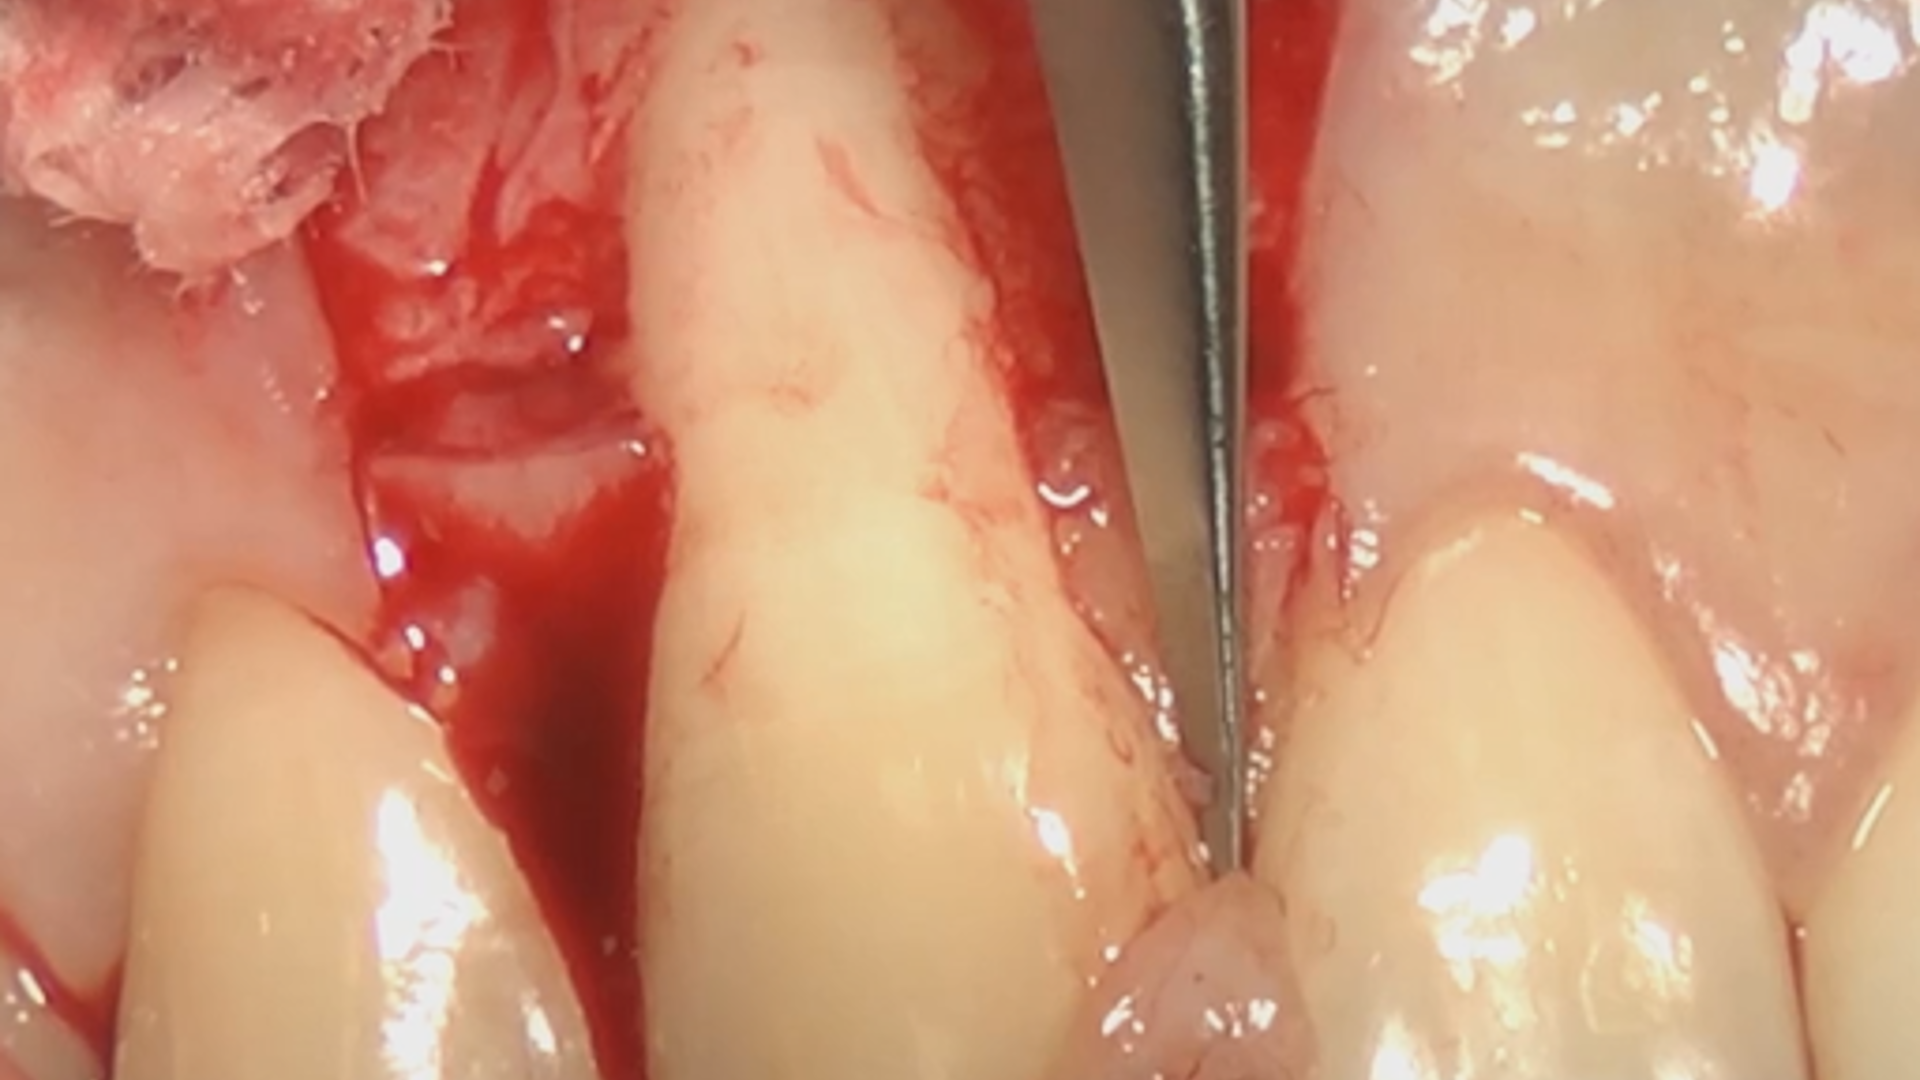

Entire surgical procedure: Coronally Advanced Flap and Connective Tissue Graft

Gingival recession treatment on a lower incisor